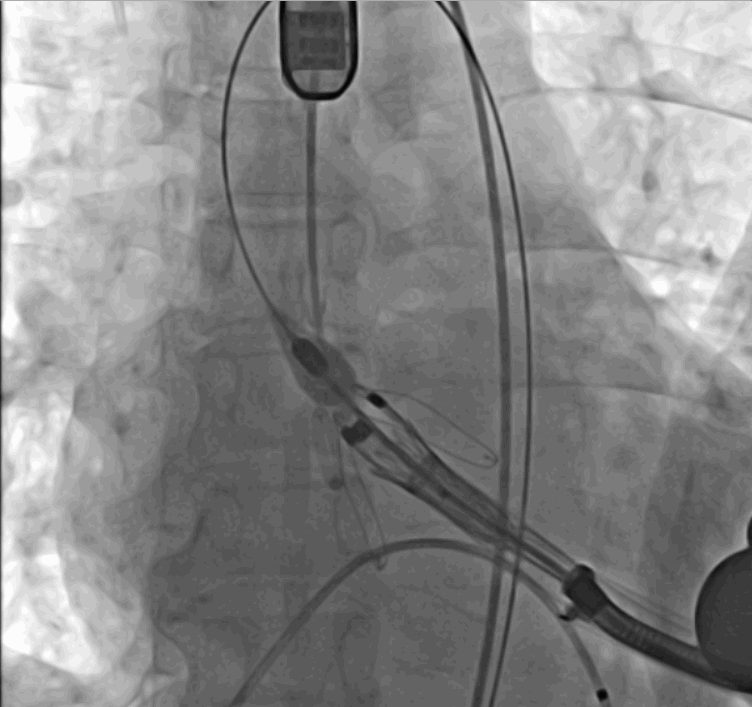

術(shù)中瓣膜釋放過程

手術(shù)采用經(jīng)心尖入路,對(duì)患者進(jìn)行全麻后,在左側(cè)心尖處做3-4cm微創(chuàng)手術(shù)切口,在DSA及超聲引導(dǎo)下手術(shù)順利完成。從導(dǎo)入器械到完成瓣膜置入,僅耗時(shí)約10分鐘。術(shù)后即刻主動(dòng)脈瓣返流程度由術(shù)前大量返流轉(zhuǎn)為消失,患者于導(dǎo)管室拔除氣管插管,次日由ICU轉(zhuǎn)入普通病房。